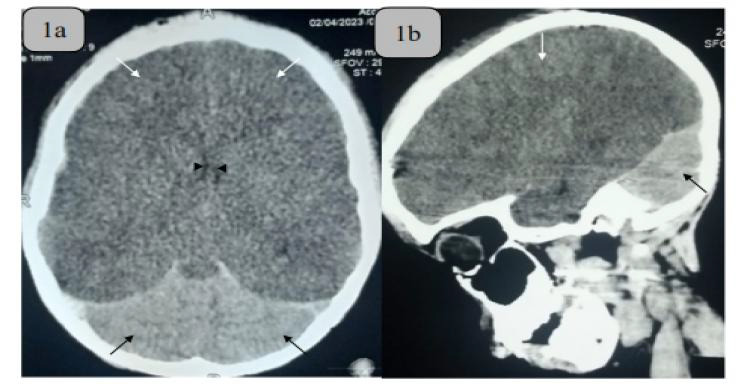

Case presentation: A fourteen-year old boy presented to our emergency department with loss of consciousness following a pedestrian road traffic accident. Physical examination revealed a critically ill boy with fever, hypotension, tachycardia, gasping respiration, GCS 3, bilateral dilated unreactive pupils, absent corneal, gag and oculocephalic reflexes. He was thus diagnosed of severe traumatic brain injury and brainstem dysfunction. He had endotracheal intubation, ventilatory and inotropic support. Cranial computerized tomography scan of the patient showed radiological features in keeping with the WCS. His clinical status remained poor until he suffered a cardiac arrest about twelve hours after admission.

Conclusion: WCS has been reported in relation to child abuse, anoxic-ischemic brain injury, inflammatory and metabolic brain disorders and trauma. It is a classical radiological description of diffuse cerebral edema alongside relatively normal cerebellar hemispheres and brainstem. Management of this pathology is symptomatic, and aims to ameliorate the associated raised intracranial pressure, control seizures and prevent cerebral infarction. The index patient, who presented 24 hours after severe head injury with associated early post-traumatic seizures, respiratory failure and brainstem dysfunction, had an unfavourable outcome consistent with previous reports of WCS. We have reported the rare but classical white cerebellum sign. It remains a grave prognosticator of cerebral injury and should be sought for in the neuroimaging of patients with acute brain insults.